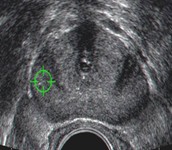

Το διορθικό υπερηχογράφημα του προστάτη (TRUS, Transrectal ultrasonography) είναι μια διαγνωστική εξέταση για την απεικόνιση του προστάτη αδένα και των γύρω περιοχών.

Η εξέταση αυτή παρέχει ακριβείς πληροφορίες για το μέγεθος και τη δομή του αδένα, την ύπαρξη φλεγμονών, υπερτροφίας ή «ύποπτων» περιοχών που μπορεί να υποδεικνύουν καρκίνο. Χρησιμοποιείται και ως οδηγός για βιοψία προστάτη. Κατά τη διάρκεια των βιοψιών προστάτη, το διορθικό υπερηχογράφημα μπορεί να ανιχνεύσει μια δυνητικά ύποπτη υπόηχη περιοχή. Το υπερηχογράφημα όμως από μόνο του δεν αποτελεί αξιόπιστη διαγνωστική εξέταση για κακοήθεια του προστάτη.